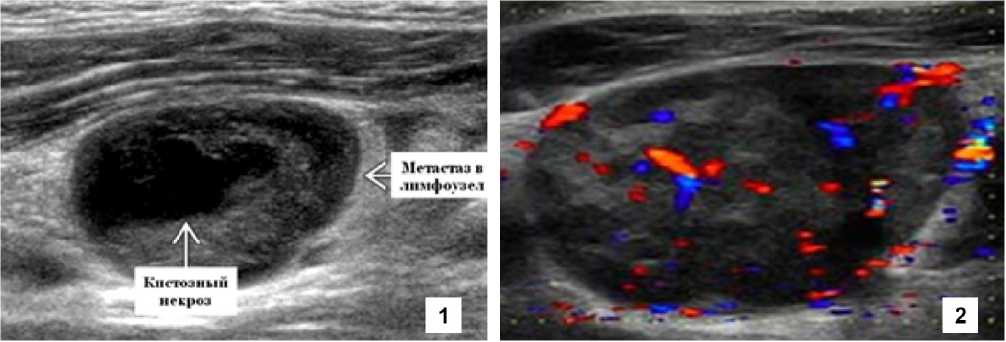

Снижение кровотока при допплерографии может быть одним из веских признаков возможной онкологической трансформации, что является основанием для проведения цитологической (гистологической) трансформации. При этом, как правило, выявляется плохая дифференцировка слоев лимфатического узла (варианты 3 и 4). Кроме того, неравномерность кровотока (рис. 2) и наличие мелких гиперэхогенных включений также могут быть служить основанием для показания к морфологической или цитологической верификации.

Р и с . 2 . Поражения лимфоузла: 1 – кистозный некроз проявляется в виде анэхогенного включения в центре лимфатического узла вместо гиперэхогенного мозгового слоя; 2 – смешанный кровоток: отмечается усиление кровотока как в воротах, так и по периферии узла, что указывает на усиление кровоснабжения (реактивная гиперплазия или структурные нарушения при метастазировании)

F i g . 2 . Lymph node lesions: 1 – cystic necrosis manifests itself as anechoic inclusion in the center of the lymph node instead of the hyperechoic medulla; 2 – mixed blood flow: increased blood flow is noted both at the gates and along the periphery of the node, indicating increased blood supply (reactive hyperplasia or structural abnormalities during metastasis)